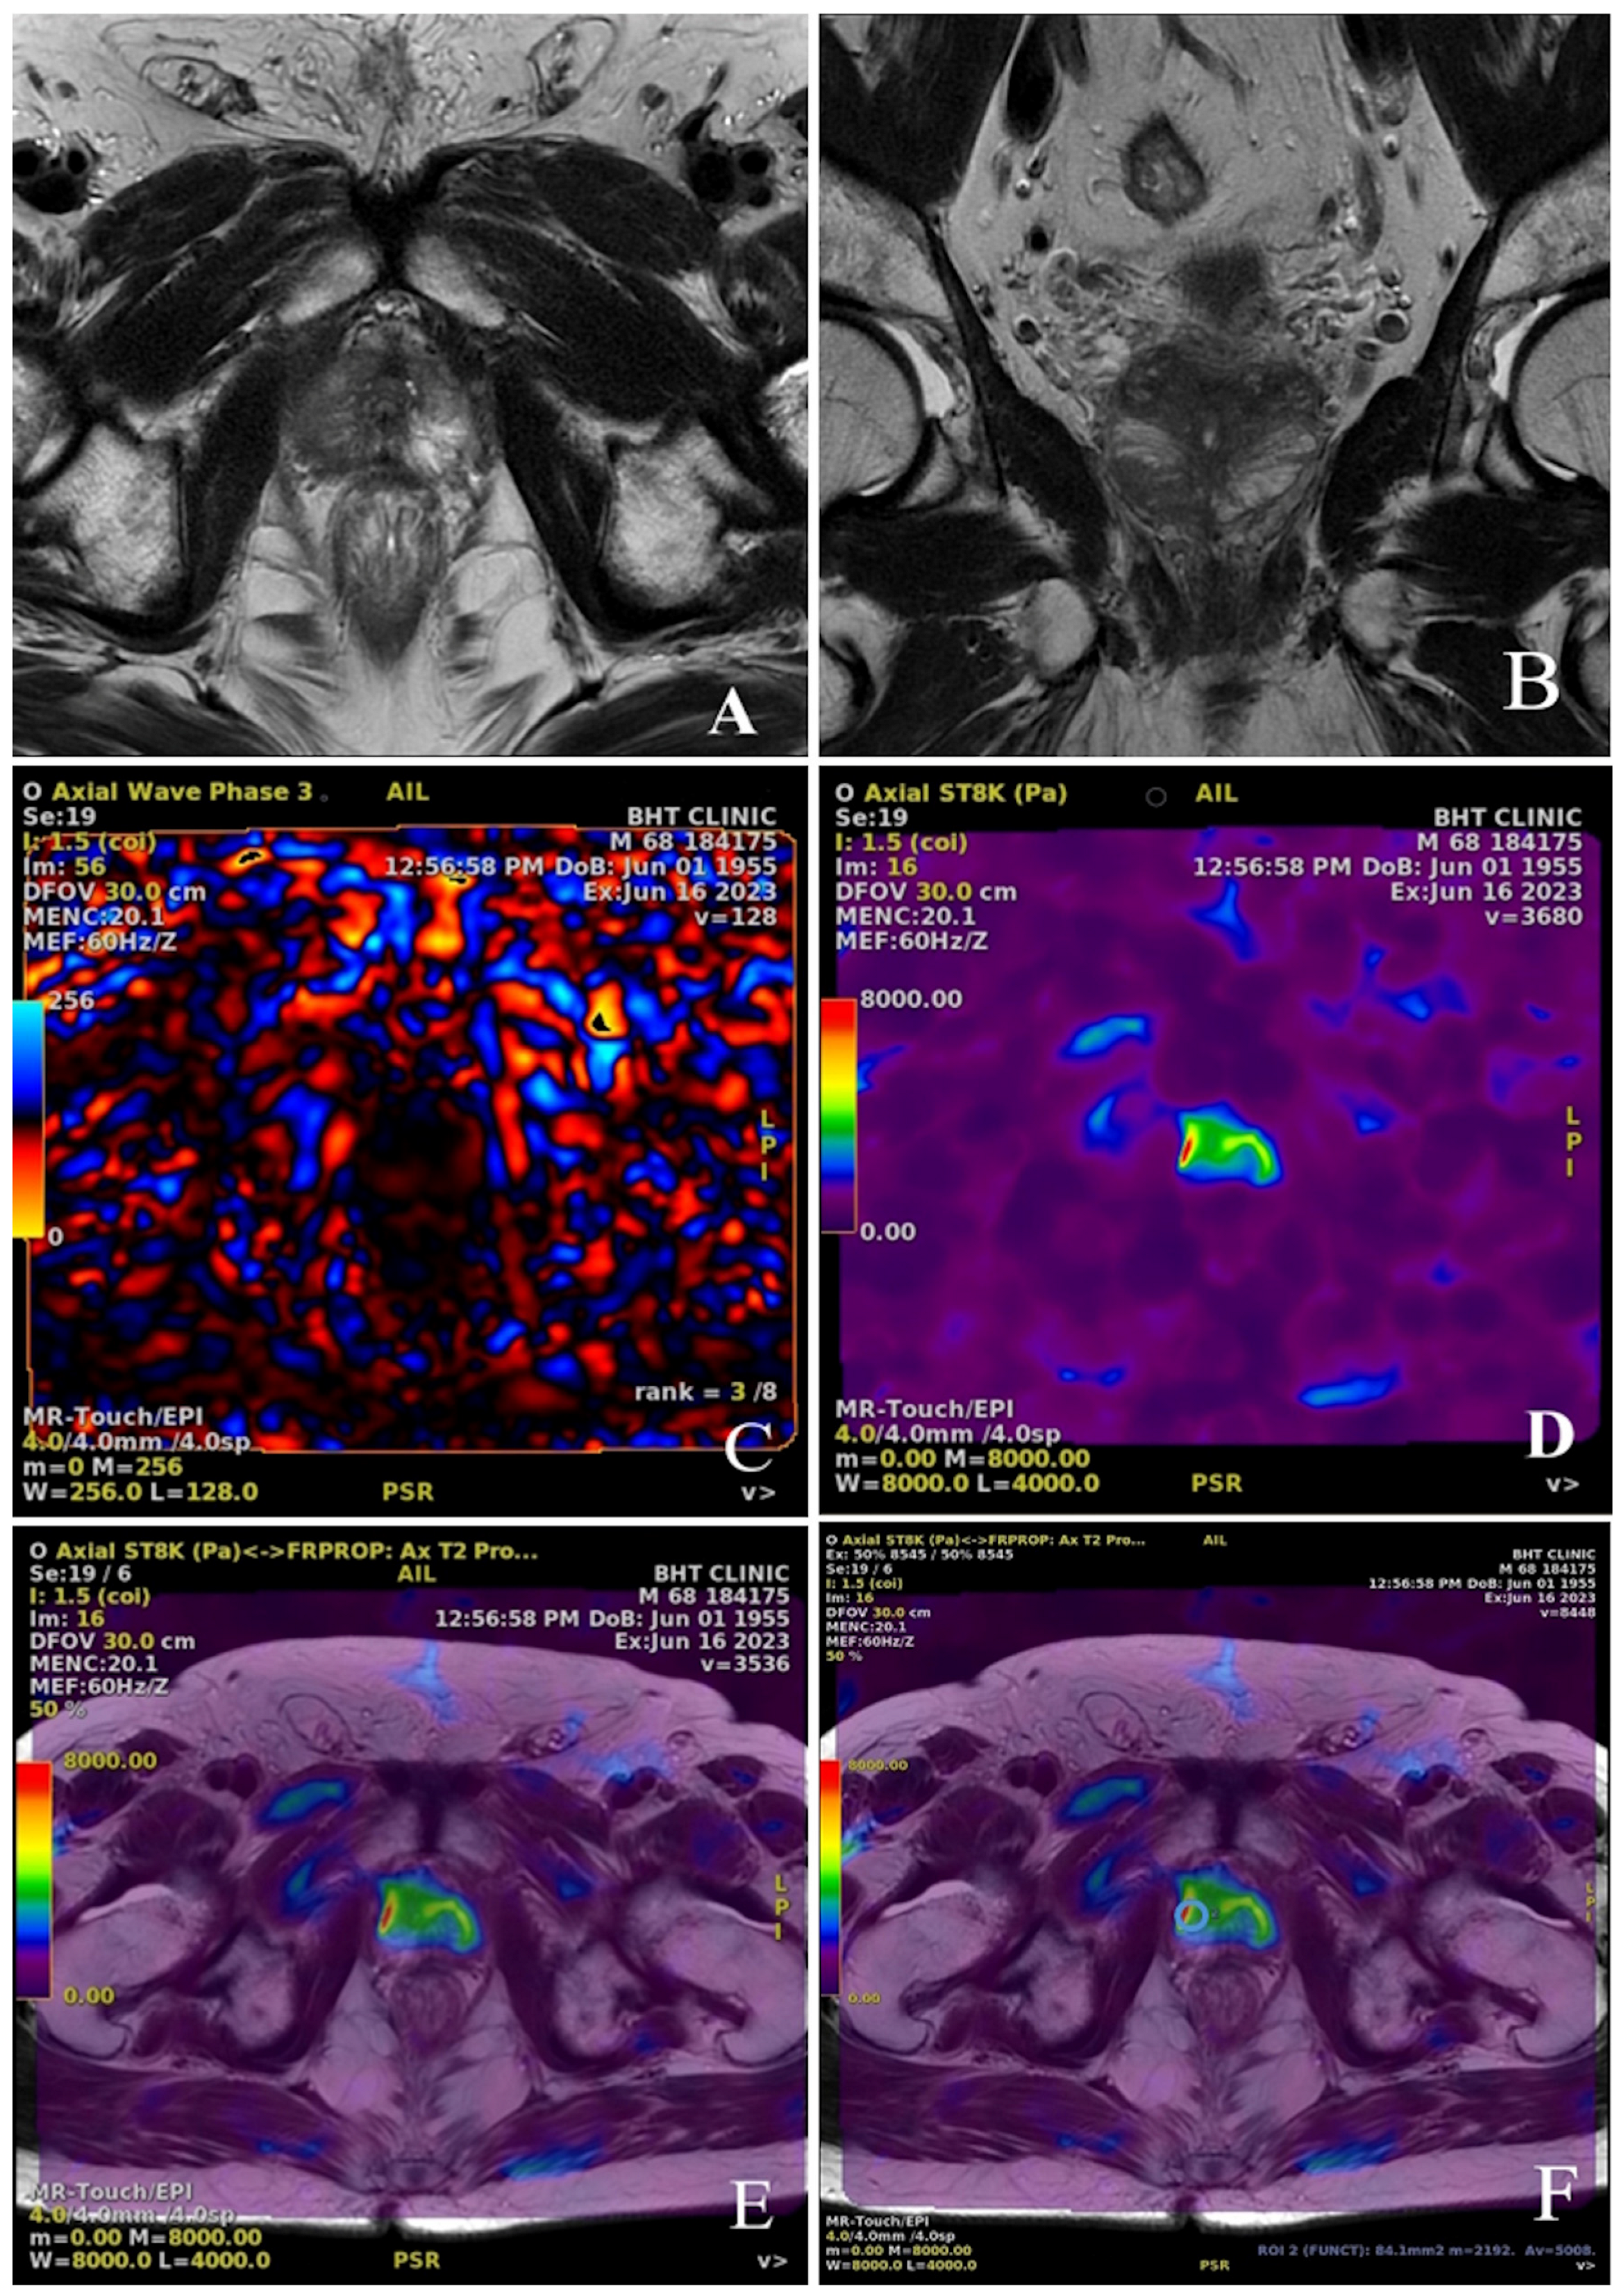

2.4. Radiological Measurements